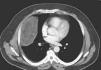

On presentation, this gentleman was fit and well. Cardio-respiratory revealed decreased air entry on the right basal lung field. The rest of examination was normal. We performed a CT-scan (Fig. 1), which confirmed the presence of a huge mass of an unidentified nature occupying the right hemi thorax. Its measurements were 17cm×13cm×10cm. A PET FDG confirmed the mass to be of normal activity with no other abnormal uptake elsewhere.